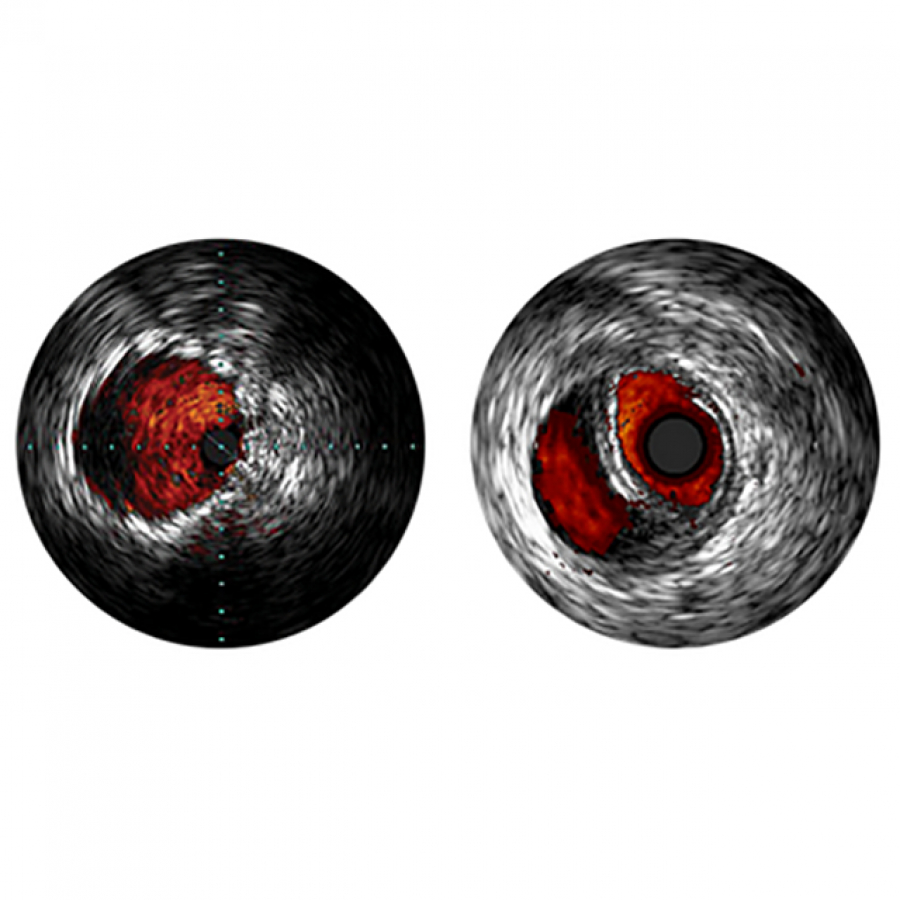

Специализированные одноразовые цифровые катетеры для проведения внутрисосудистых ультразвуковых исследований (ВСУЗИ) в периферических артериях. Обеспечивают получение высокодетализированных изображений в режиме реального времени для оценки состояния сосудов нижних конечностей, сонных и других периферических артерий.

VUS – Внутрисосудистое ультрозвуковое исследование (ВСУЗИ). Используется для определения состояния коронарного русла на диагностическом этапе и оценки/опти-мизации результатов проведения чрезкожного коронарного вмешательства. Миниатюрный ультразвуковой датчик, расположенный на катетере, по проводнику проводят в просвет артерии и осуществляют качественный и количественный анализ просвета сосуда и сосудистой стенки на неизмененных и пораженных участках, оце-нивают состояние сегментов артерии во время и после эндоваскулярных операций (баллонной ангиопластики, стентирования, атерэктомии).